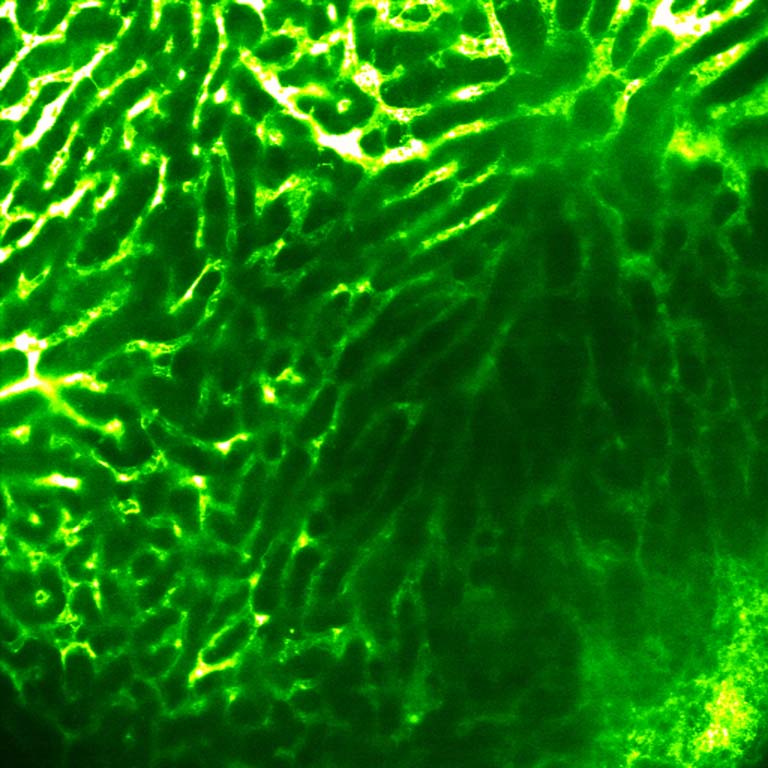

This image shows how we can use an implant of a biomaterial (on the right side of the image) seeded with vascular cells as scaffold to fix and splice a damaged vascular area in a living donor of liver (on the left side of the image) in order to regenerate the tissue faster and for a faster recovery of hepatic function. The image is part of a project focused to develop implants for cell therapy able to improve liver regeneration and function after liver transplantation in donor and receptors.